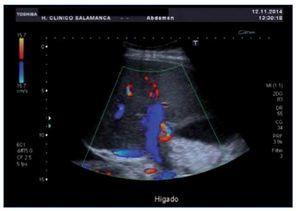

Ante la sospecha inicial de IRA de origen nefrotóxico en una paciente con bajo volumen efectivo circulante, se realizó ajuste posológico, se pautaron expansores del plasma, se forzó la diuresis y se solicitaron una radiografía de tórax y una ecografía renal urgentes (figura 1) que mostraron derrame pleural, ascitis en cuantía discreta, hígado aumentado de tamaño con signos de hepatopatía difusa, inversión del flujo portal y aumento de calibre de la arteria hepática.

Figura 1. Ecografía renal de la paciente en el momento del diagnóstico del SOS hepático. Destaca la inversión del flujo portal y aumento de calibre de la arteria hepática.

En ese momento, el diagnóstico diferencial se estableció con la EICH aguda, que se excluyó al no existir manifestaciones clínicas a otros niveles, con el síndrome de Budd-Chiari, que se descartó al no existir datos ecográficos sugestivos de trombosis de las venas suprahepáticas, y con la nefro/hepatotoxicidad medicamentosa, no presente en ese momento por tener la paciente niveles de medicación dentro del rango terapéutico (tabla 2). Se diagnosticó de SOS hepático con IRA secundaria por síndrome hepatorrenal de acuerdo con los criterios clínicos de Baltimore7 apoyados por los hallazgos ecográficos. En las 24 horas siguientes, tras cesar la clínica hemorrágica, se inició tratamiento con defibrotide, que se mantuvo durante 19 días (día +32) hasta que los signos/síntomas de la enfermedad desaparecieron. El síndrome hepatorrenal se trató con restricción hídrica, expansores del plasma (12 concentrados de hematíes y albúmina), diuréticos (espironolactona y furosemida) y terlipresina. A las 48 horas del diagnóstico, la paciente asoció taquipnea intensa e incremento en las necesidades de oxigenoterapia, que obligó a realizar paracentesis para disminuir la presión intraabdominal. Durante el ingreso, la paciente también recibió transfusión de 40 unidades de plaquetas. La evolución clínica y analítica (figuras 2 y 3) de la paciente fue buena, siendo dada de alta el día +36 con normalización de la función renal y hepática. El control ecográfico posterior (día +28) objetivó flujo portal alternante centrípeto-centrífugo, con normalización del flujo en control ecográfico realizado tras el alta (día +90). La reevaluación de la paciente y la enfermedad hematológica, mediante PET-TC, el día +90 reflejó que la paciente estaba en remisión completa.

El diagnóstico de SOS es clínico, y habitualmente no es preciso ni posible realizar biopsia renal o hepática, dada la trombopenia y los trastornos de la coagulación. La medición del gradiente de presión venosa hepática a través de la vena yugular es el método diagnóstico más preciso para confirmar y evaluar la gravedad del SOS hepático. La ecografía puede ayudar a la hora de realizar el diagnóstico diferencial; pone de manifiesto la existencia de hepatomegalia, ascitis y atenuación o inversión del flujo venoso hepático. En nuestro caso, la ecografía contribuyó al diagnóstico de forma significativa. Para diagnosticar el SOS hepático se recurre a los criterios de Seatle14 (dos o más de los siguientes eventos en los 20 días postrasplante: bilirrubina > 2 mg/dl, hepatomegalia o dolor en el hipocondrio derecho, ganancia de peso por retención de líquidos > 2 % del peso basal) o de Baltimore7 (bilirrubina > 2 mg/dl dentro de los 21 días posteriores al trasplante más al menos dos de los siguientes criterios: hepatomegalia, ascitis, ganancia de peso > 5 % respecto al peso pretrasplante). La aproximación clínica a la gravedad del SOS hepático se establece de acuerdo con las siguientes variables: bilirrubina total (leve < 5 mg/dl, moderada 5,1-8 mg/dl, grave > 8 mg/dl), AST (leve < 3 x normal, moderada 3-8 x normal, grave > 8 x normal), ganancia de peso (leve < 2 %, moderada 2-5 %, grave > 5 %), creatinina sérica (leve normal, moderada < 2 x normal, grave > 2 x normal), y tiempo de instauración (leve 6-7 días, moderado 4-5 días, grave 2-3 días)3,7,8. En nuestro caso, la paciente cumplía tanto los criterios clínicos de Seatle14 como de Baltimore7, y presentaba un SOS hepático grave.